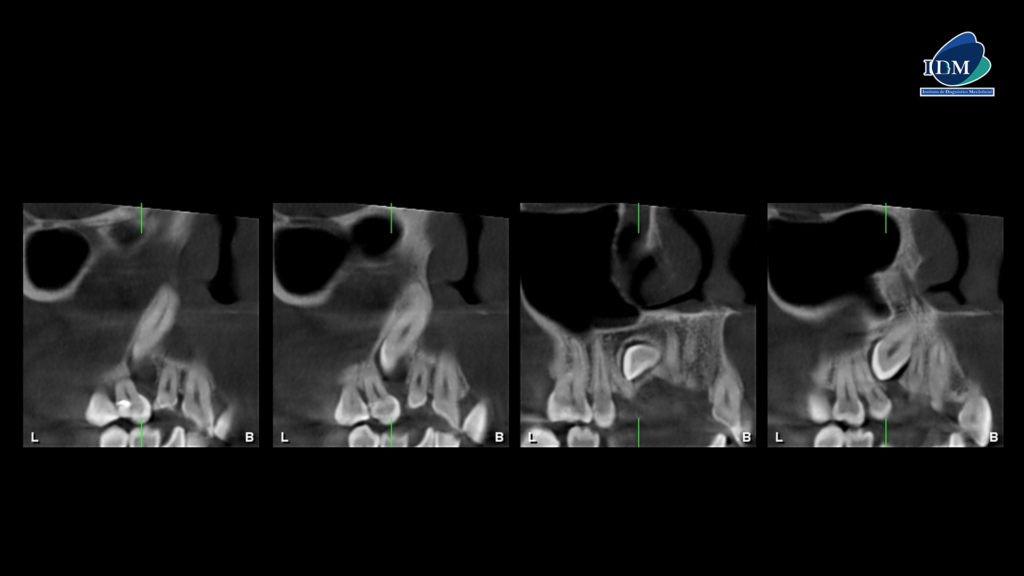

Así mismo en la tomografía volumétrica de haz se evidencia que dicha pieza esta distoangulada con el segmento coronario orientado hacia palatino y el segmento radicular orientado hacia vestibular, conservando el espacio del ligamento periodontal en toda su trayectoria.

CORTES TRANSAXIALES